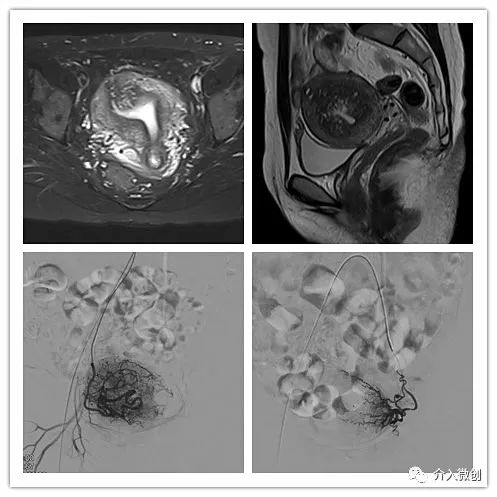

例1

青年女性患者,痛经近10年,近5年痛经明显加重。确诊为子宫腺肌症(弥漫型),经放置曼月乐、注射亮丙瑞林等妇科保守治疗,症状缓解不理想,痛经进行性加重,严重困扰工作与生活。

- 行子宫腺肌症介入栓塞治疗

- 插管至右侧髂内动脉造影,显示右侧子宫动脉

- 插管至右侧子宫动脉,显示子宫右侧病灶情况

- 插管至左侧子宫动脉,显示子宫左侧病灶情况

- 术前MRI显示子宫明显增大,病灶主要位于子宫前壁

术前MRI显示子宫明显增大,病灶主要位于子宫前壁

- 患者术后1个月痛经明显缓解。术后3个月复查MRI显示子宫明显缩小,前壁病灶萎缩坏死。

术后3个月复查MRI显示子宫明显缩小,前壁病灶萎缩坏死